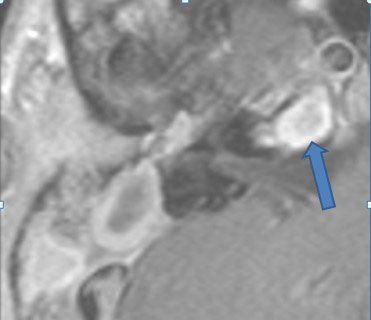

There is evidence of thrombosis, thrombophlebitis or other occlusive or inflammatory process of the sigmoid sinus, transverse sinus, the vein of Labbe’ or jugular bulb

There is evidence of thrombosis, thrombophlebitis or other occlusive or inflammatory process of jugular vein.